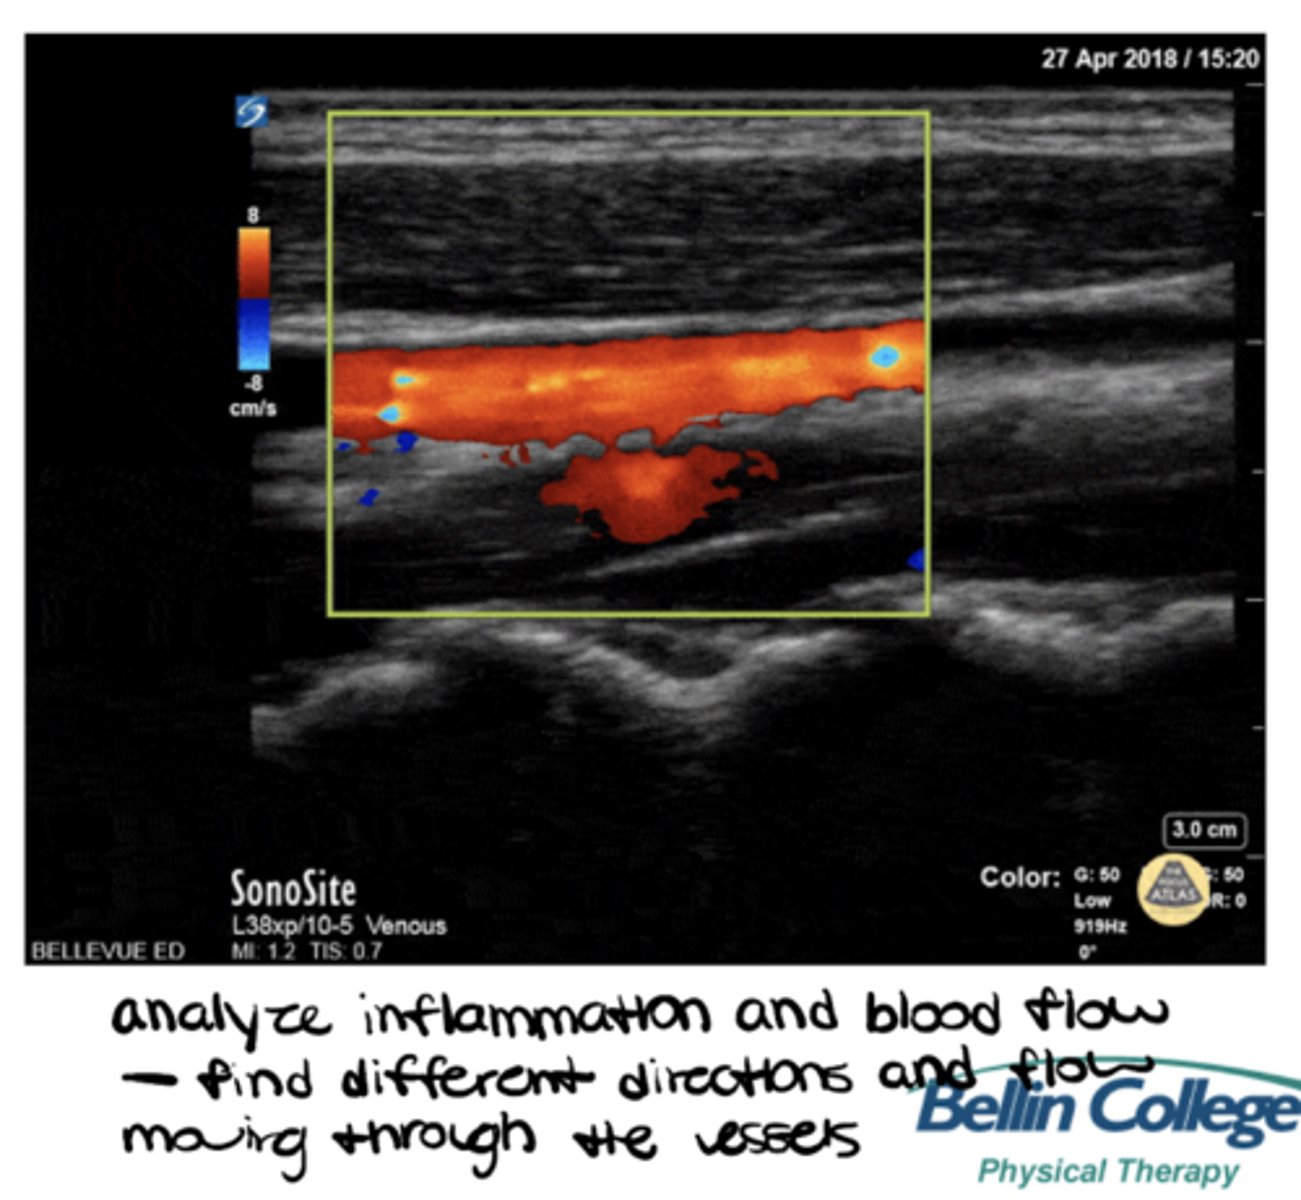

___________: mode of ultrasound that records blood flow (veins and arteries) and inflammation

Doppler (fluid mode)